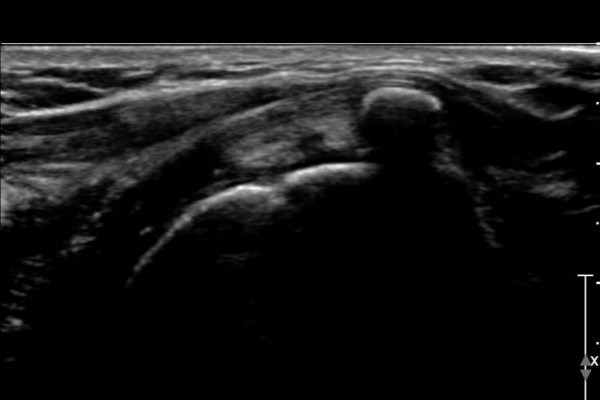

°ß°©ÇÏ±Ù°Ç Á¾´Ü¸é°Ë»ç(»çÁø 2)¿Í ȸ´Ü¸é°Ë»ç(»çÁø 2)¿¡¼­ ÈĹæÀ½¿µÀ» º¸ÀÌ´Â °í¿¡ÄÚ ¼®È¸°¡

°üÂûµÈ´Ù. Åë»óÀûÀÎ °ß°©ÇÏ±Ù°Ç Á¾´Ü¸é°Ë»ç¿¡¼­´Â °ß°©ÇÏ±Ù°Ç »óºÎ ¼®È¸È­·Î º¸ÀÌÁö¸¸ Ⱦ´Ü¸é°Ë»ç·Î

º¼ ¶§ °ß°©ÇÏ±Ù°Ç ÇϺο¡ ¹ß»ýÇÑ ¼®È¸ÀÓÀ» ¾Ë ¼ö ÀÖ´Ù.